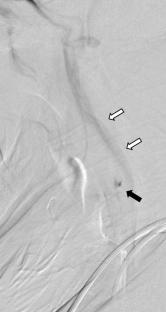

Carotid web: identifying an often-overlooked cause of stroke during endovascular therapy

Abstract Image